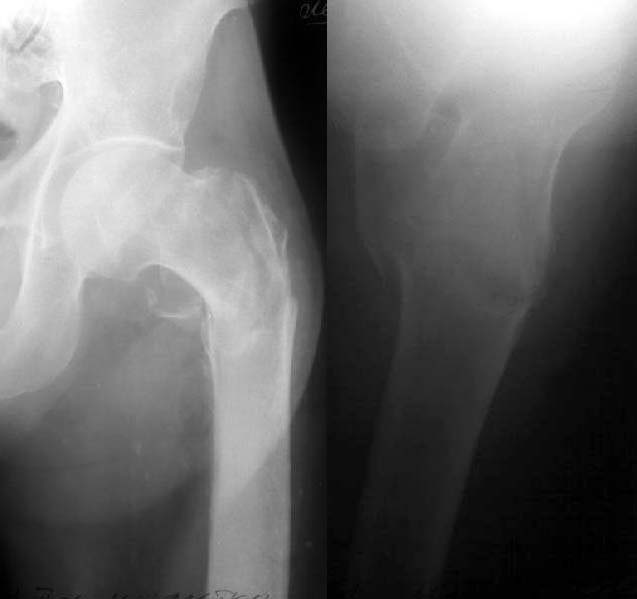

Most of the mentioned is unavalable in our institution :(. We still have not done yet any case with Ender-like nails so didn't try it for the first time in this patient. So external fixation was performed (see attachment).

Two hours after the surgery the patient was sitting and happily smoking . Yesterday he tried to walk with crutches, but he is too weak for this, he can stand only. This morning he left for home.

THere's more than one way to skin a cat, I guess. THe reduction looks fine on those films. It's too bad you couldn't get a picture of him smoking - that would've been great.

Thanks for posting the post-op images. I've never seen anything like that before. It looks pretty nice, actually. Nice case. Y'all are the Ilizarov kings.